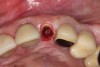

A 65-year-old male patient presented to the office with a fractured maxillary left lateral incisor (Figure 16). Radiographic analysis revealed minimal buccal bone. Having deemed the tooth nonrestorable, the clinician presented several options to the patient, which they carefully reviewed together. A socket-shield approach was selected with the goal of maintaining existing gingival zenith long-term.

Fig 16. Patient presented with fractured maxillary left lateral incisor. Radiographic analysis (not shown) revealed minimal buccal bone. A socket shield was planned during tooth extraction to preserve gingival contours.

Figure 16